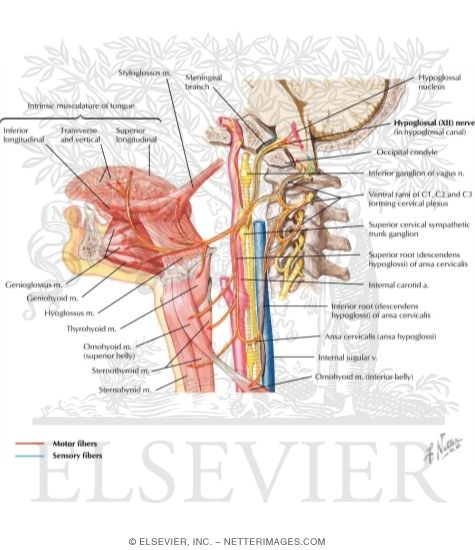

The Hypoglossal Nerve (CN XII) – Course – Motor – TeachMeAnatomy

Hypoglossal Nerve (CN-XII)

Neuroanatomy, Cranial Nerve 12 (Hypoglossal) – StatPearls – NCBI Bookshelf

Hypoglossal Nerve (CN-XII)

Hypoglossal Nerve (XII) and Canal

Hypoglossal Nerve (CN-XII)

Hypoglossal Nerve (CN-XII)